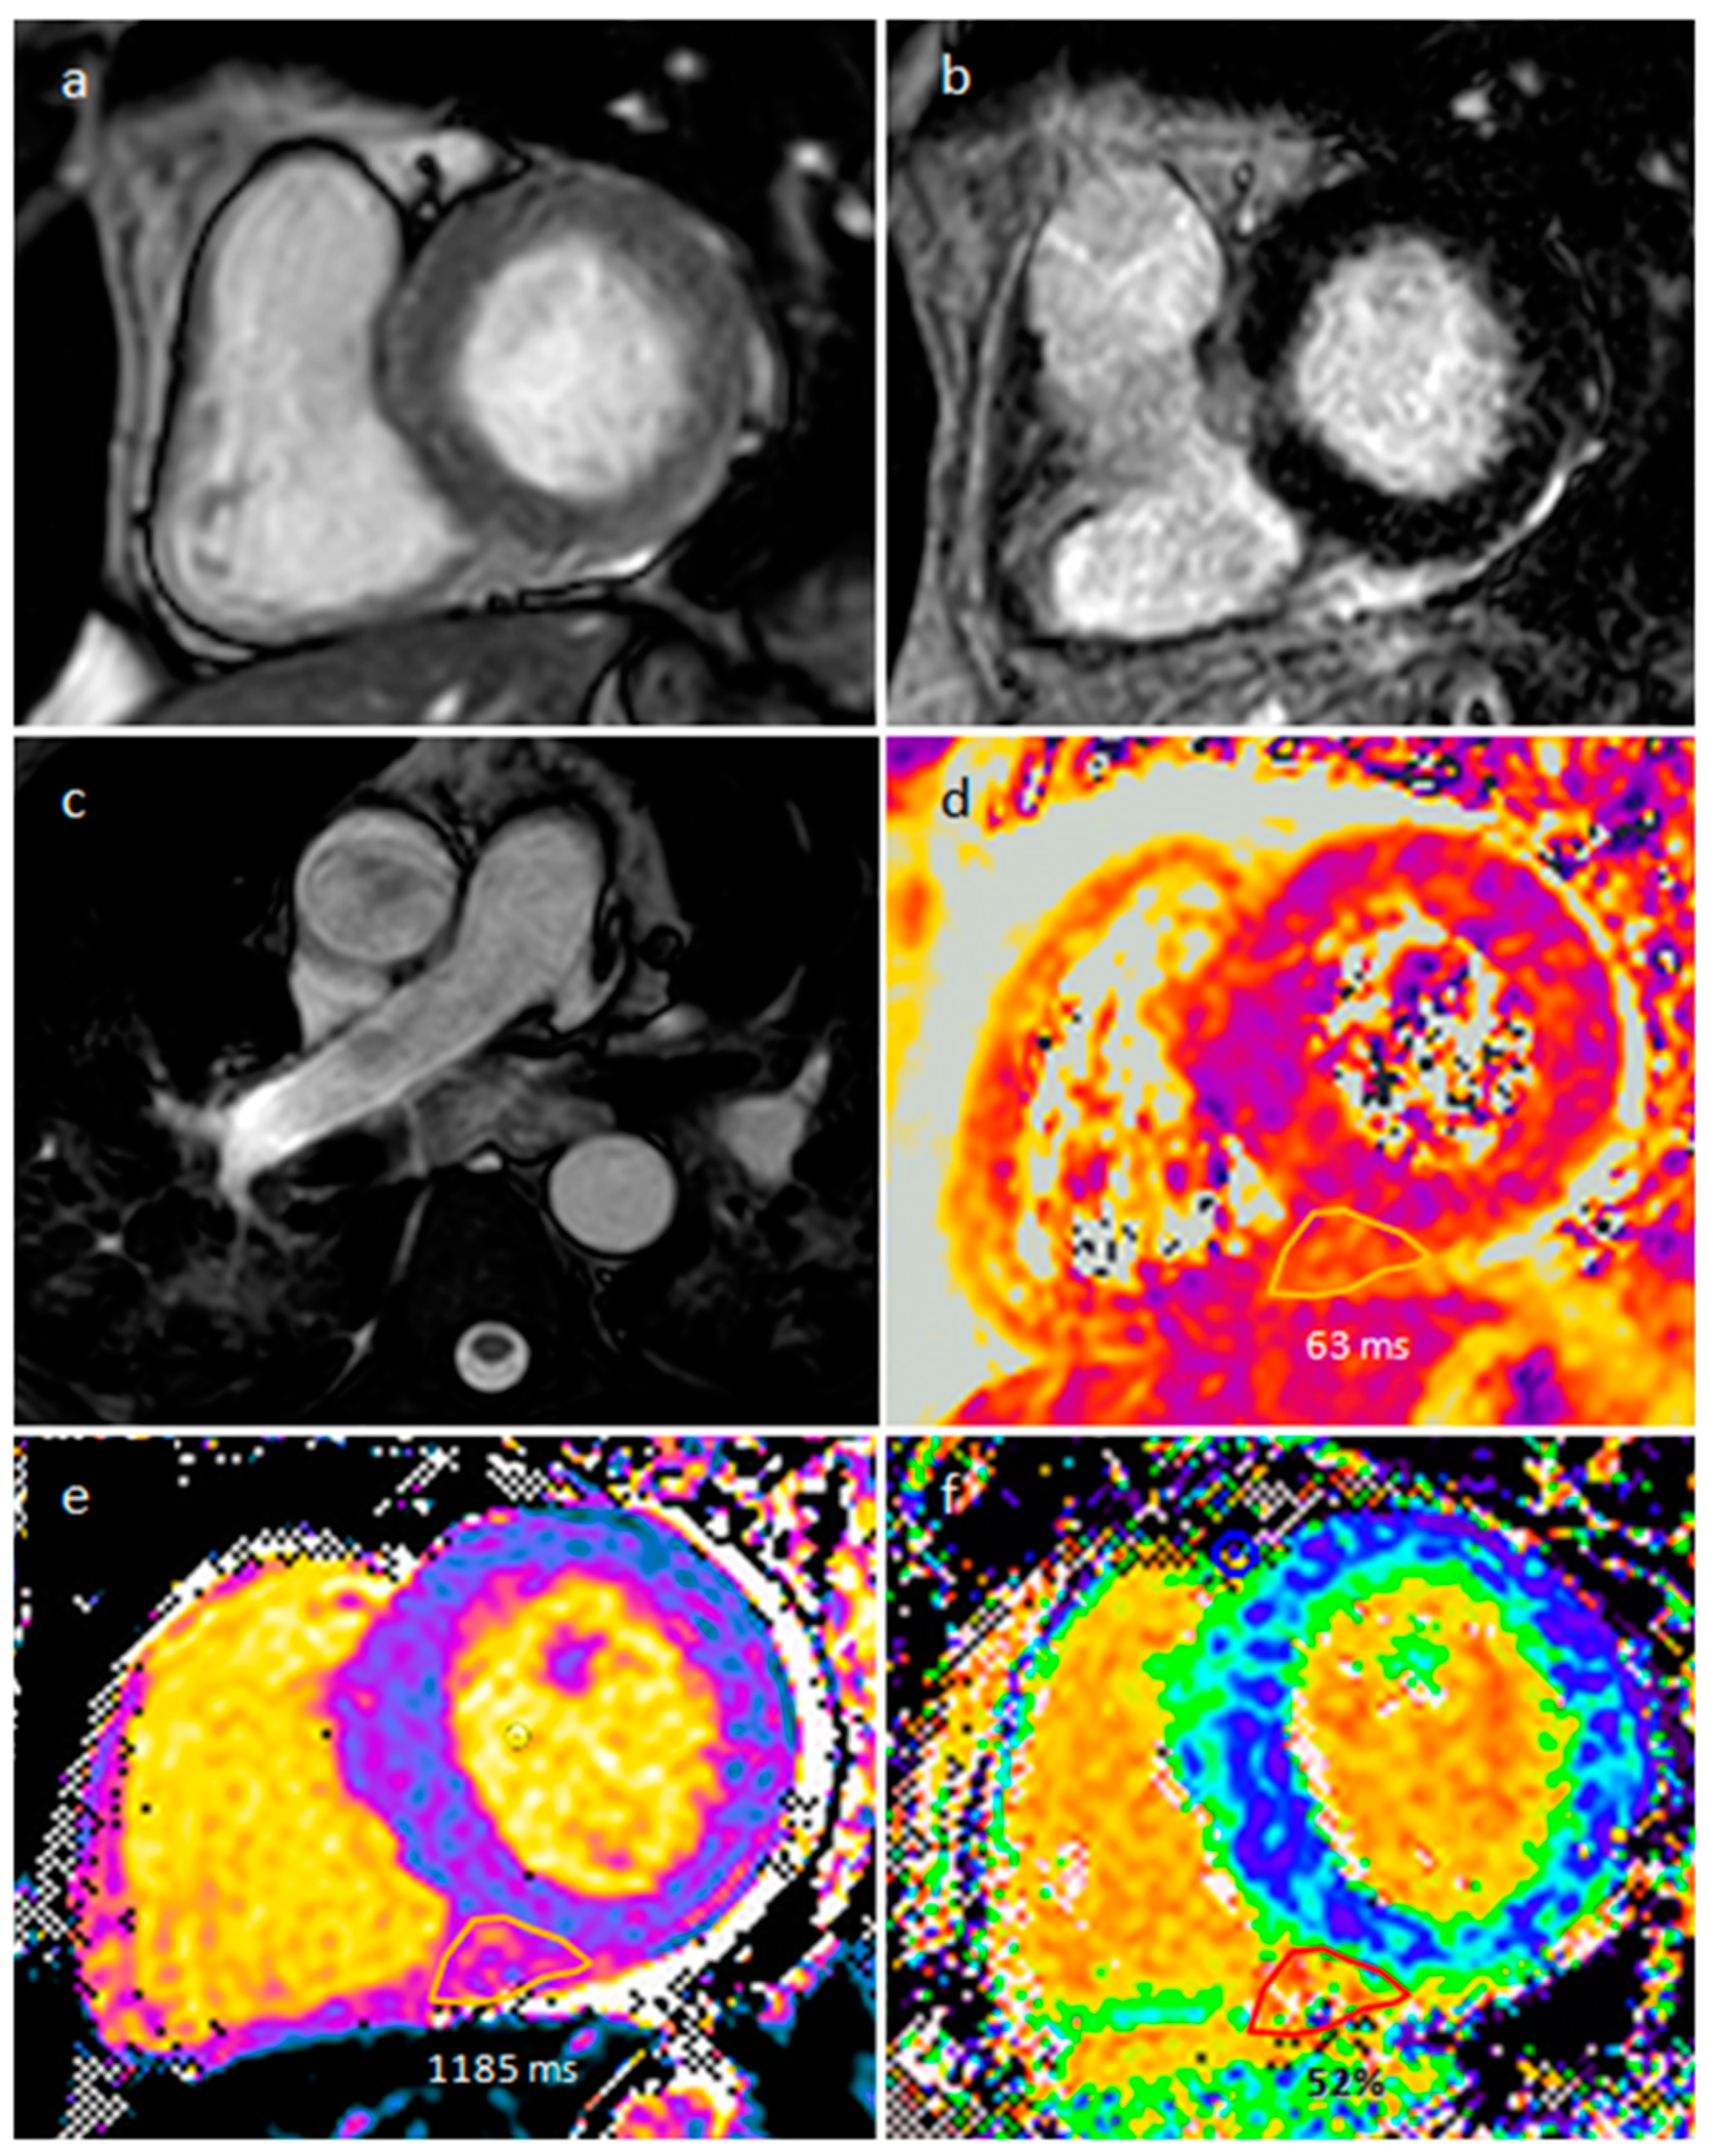

4.1. Myxoma

- Nasser, S.B.; Doeblin, P.; Doltra, A.; Schnackenburg, B.; Wassilew, K.; Berger, A.; Gebker, R.; Bigvava, T.; Hennig, F.; Pieske, B.; et al. Cardiac Myxomas Show Elevated Native T1, T2 Relaxation Time and ECV on Parametric CMR. Front. Cardiovasc. Med. 2020, 7, 602137. [Google Scholar] [CrossRef]

| Myxoma | Adulthood. Carney complex. | LA | Usually, asymptomatic. Rarely, intracardiac obstruction, embolic events and constitutional symptoms | Mobile mass arising from the IAS | Globular or spherical, with a friable surface and heterogeneous internal echogenicity | Heterogeneous, low attenuation, may be calcified | Isointense T1w, High T2w, heterogeneous LGE |